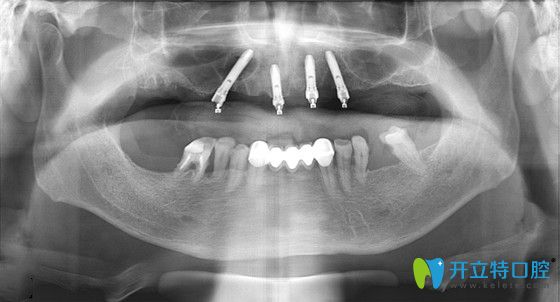

張大爺在東營(yíng)鉑爾口腔做種植牙后的CT片

張大爺即刻負(fù)重手術(shù)過程全記錄:首先,吳院長(zhǎng)運(yùn)用了三維數(shù)字軟件,精準(zhǔn)的測(cè)量了張大爺?shù)难啦酃敲芏?、高度、寬度等信息,確定了種植位置,經(jīng)過1個(gè)多小時(shí),復(fù)雜而有序的專業(yè)操作后,完成了種植體的種植操作;然后又為張大爺安裝了基臺(tái)、牙冠;當(dāng)天回到家就能吃東西啦!